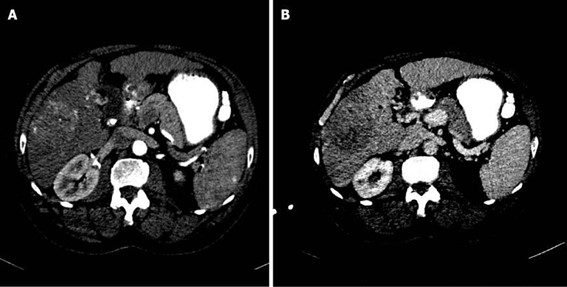

El reforzamiento en anillo (hipercaptación periférica) o incluso menos de 25% de la lesión, y es más frecuente en nódulos mayores a 3 cm. En la fase venosa portal puede permanecer invariable cuando los nódulos son pequeños. Puede presentar un reforzamiento progresivo: existiendo el máximo realce en fases tardías (más frecuentes en nódulos de mayor tamaño). También puede demostrar un reforzamiento continuo con área central que no capta el medio de contraste. En la fase tardía la región central puede mostrar un reforzamiento variable en función de la existencia de fibrosis (aumento de la captación) o necrosis coagulativa (sin captación del contraste).(18-22)

La evidencia de las lesiones hepáticas obedece tanto al número y localización dentro del hígado, como a la presencia o no de enfermedad extrahepática. Esto último es importante en el proceso de selección de aquellos pacientes a los que se les debe o no ordenar una cirugía hepática. En la tomografía sin contraste las metástasis suelen ser iso o hipodensas respecto del resto de parénquima, salvo en casos de sangrado o calcificación intralesional en que pueden ser hiperdensas. Podemos observar calcificaciones en metástasis de tumores mucinosos del tracto gastrointestinal o en metástasis de ovario, mama, pulmón, riñón y tiroides.(18) Las metástasis suelen tener el mismo comportamiento que el tumor de origen, suelen ser hipovasculares en tumores de colon, pulmón, adenocarcinoma de páncreas y en tumores de vejiga y próstata. Se observan lesiones hipervasculares en tumores primarios de tiroides, tumores neuroendócrinos (carcinoide, tumor de islotes pancreáticos, feocromocitoma) y en melanoma, cáncer renal, coriocarcinoma y sarcomas.(18-19)

Dentro de los patrones de reforzamiento de las metástasis lo más frecuente que podemos encontrar en fase arterial es la captación periférica y continua (por efecto de parasitación de la lesión y reacción desmoplástica/inflamatoria del parénquima adyacente), metástasis homogéneamente hipercaptantes (suelen ser menores de 1,5 cm), metástasis heterogéneas por fibrosis y necrosis central (> 3 cm) o con mínima captación periférica (lesiones hipovasculares).(18) En las fases portal y venosa tardía el patrón más frecuente es la captación progresiva incompleta. En menor grado se observan lesiones que se hacen isodensas con el resto de parénquima o persistencia de una mínima captación periférica (Anexo 17). El fenómeno de lavado (washout) periférico se ha descrito como hallazgo típico de metástasis, consiste en la desaparición del contraste en la periferia de la lesión en fases retardadas, es más frecuente en las metástasis hipervasculares, especialmente en tumores neuroendocrinos. Supone una mejor vascularización arterial y venosa en la periferia, donde se sitúa el tumor viable, respecto al centro de fibrosis o necrosis.(18-22)